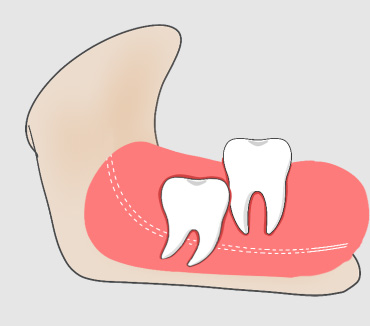

什么是侵犯邻牙?

智齿萌发的空间不足,倒在第二大臼齿上。通常患者不自知,而由牙医以X光诊断得知。

智齿侵犯邻牙的危害

智齿如果一直朝着挤压邻牙的方向生长,就会导致邻牙破坏、牙根吸收,最终两颗牙齿都保不住。